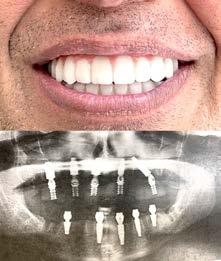

# 9 (2024) • 12 мая Газета «Диаспора» – все о нас с вами ПО ВОПРОСАМ РАЗМЕЩЕНИЯ РЕКЛАМЫ ОБРАЩАЙТЕСЬ ПО ТЕЛЕФОНУ: (916) 487-9701 или (916) 705-0739 10 Замещение всех зубов на 4-х, 6-ти имплантах Одиночные импланты Несколько имплантов ИМПЛАНТАЦИЯ ЗУБОВ Установка одного импланта от FREE Consultation and CT-Scan Лучшее качество услуг и материалов по разумной цене! Консультация и 3D снимок в подарок. 911 Reserve Dr., Ste #150, Roseville, CA 95678 | Phone: (916) 827-3605 $998* (916) 827-3605 Высококлассные услуги по Зубной Имплантации в современной клинике, лимиторованной на установку имплантов. * - установка 1 (одного) импланта не включая абатмент и коронку. Имплантация будет производится одним из специалистов клиники под руководством доктора Александра Антипова, челюстно-лицевого хирурга. Цена указана для пациентов, оплачивающих наличными. Все-на-5-ти имплантах + несъемные зубы за 1 день Одна из недавних операций: